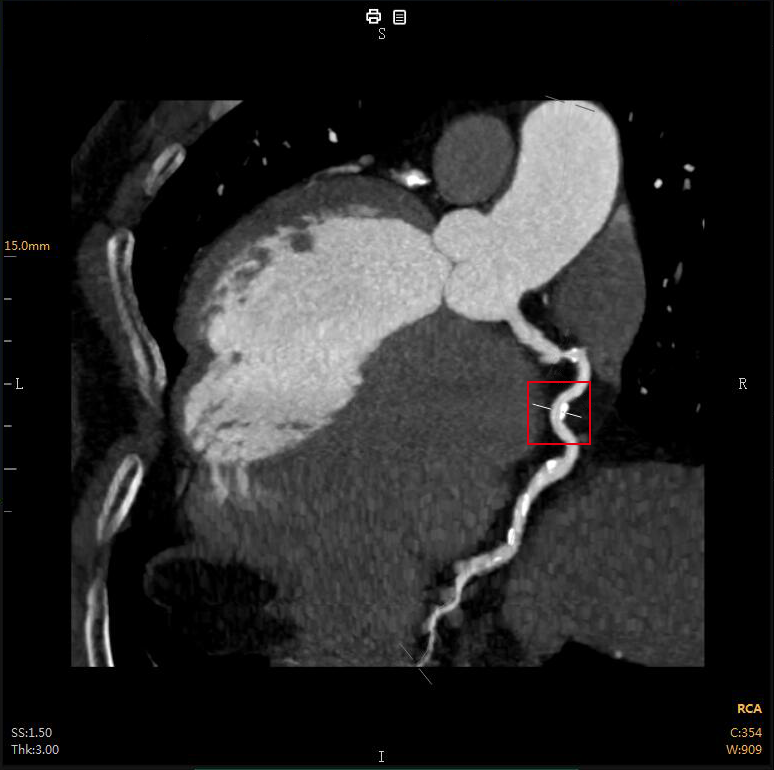

“CTA冠脈全自動(dòng)診斷”

Automatic Coronary Diagnosis

冠心病、心肌梗死是危害極大的疾病

CTA冠脈動(dòng)脈造影以幾乎無(wú)創(chuàng )的方式

成為冠心病的首選檢查

全自動(dòng)圖像重建/分割

全自動(dòng)量化測量

全自動(dòng)結構化報告

全自動(dòng)膠片及電子膠片輸出

云端極速一氣呵成

云端AI的CTA冠狀動(dòng)脈全自動(dòng)診斷

重構了CTA冠脈檢查的極簡(jiǎn)流程